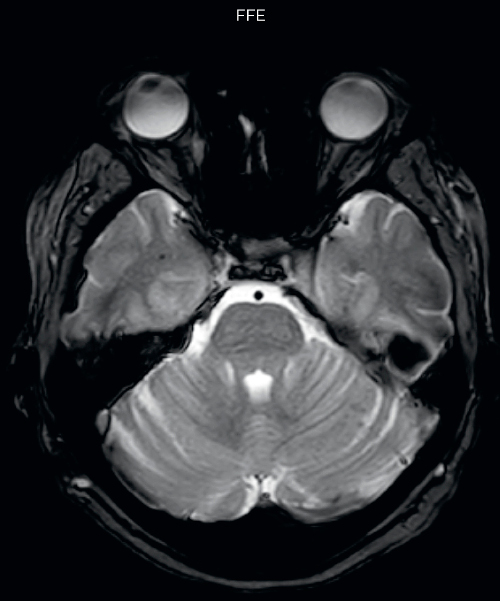

Gradient echo imaging and SWIp are compared in a patient with radiation-induced foci of hemosiderin deposition. A greater number of small foci is seen on the SWIp image. Ingenia 3.0T